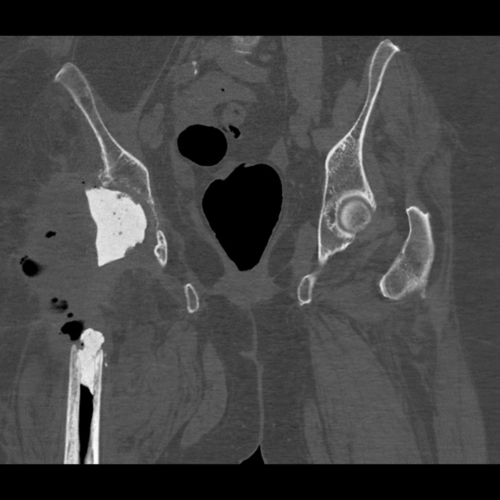

CT scan - scroll through the post-operative computer tomography scan. This shows the acetabular component with good contact to the host bone and a well-positioned proximal femoral replacement.